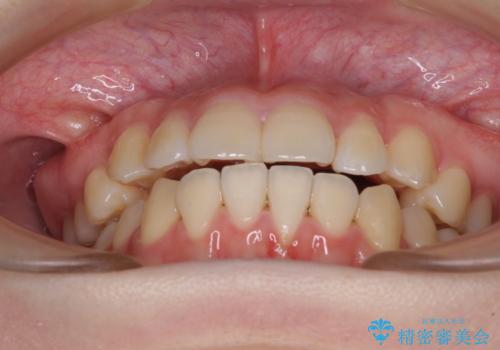

カリエール・ディスタライザーとインビザラインを用いた八重歯の改善

- 前歯の叢生と上顎左右の八重歯を気にして来院された患者様です。

奥歯の咬み合わせを見ると、左側は上顎が下顎に対して相対的に前方にあり、上下の前歯が接触していない状態でした。

咬み合わせを改善するためには、左側上顎臼歯を後方に移動させた咬み合わせにする必要があります。

インビザライン単体で改善することも可能性もありますが、インビザライン単体で達成する可能性が低いと考えられたため、カリエール・ディスタライザーという補助装置を併用して、より確実性を上げることとしました。

奥歯の咬み合わせを改善しながら、並行してインビザラインで歯列を整えることとしました。

カリエールディスタライザーを併用したことで、左側臼歯の咬み合わせを確実に改善させることができました。